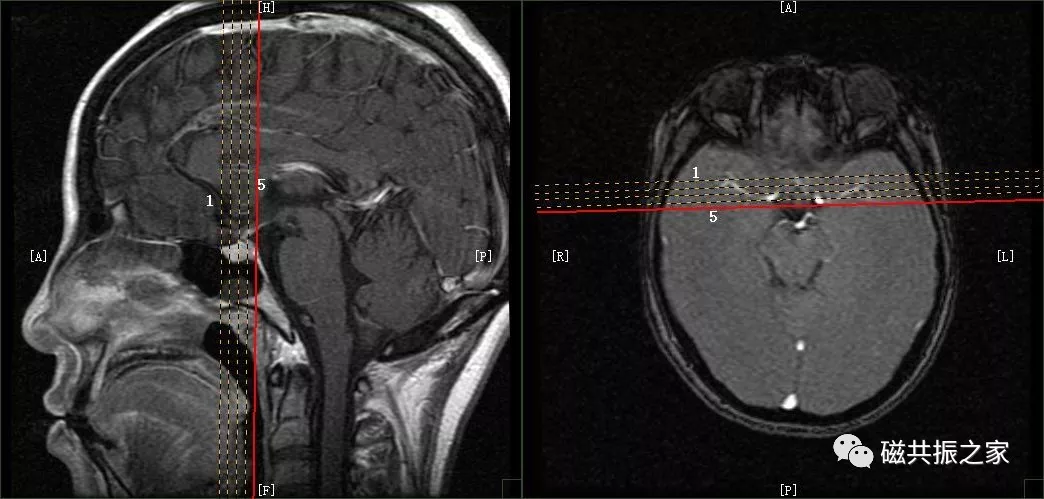

冠状位:CORDynamicT1FSE冠状位T1多期动态增强序列

以矢状位和横断位作为参考定位。定位方法同上面的平扫序列,双侧对称扫描,扫描范围包括整个垂体,为了保证时间分辨率,扫描层数不宜过多,5-7层。注射对比剂前先扫描一期蒙片,暂停,然后注射对比剂的同时开始连续的动态扫描(1.5T:8-10期,每一期20S左右最佳,3.0T:15-20期,每期10S左右最佳),整个动态增强序列扫描3min左右即可。

动态增强通常采用冠状面扫描。注射对比剂前扫描一期蒙片的目的:评估扫描所得的图像质量是否能满足诊断要求,包括范围、信噪比,伪影等。

为了保证足够的信噪比应适当的加大FOV,减小矩阵。

为了保证时间分辨率扫描层数不宜过多,回波链可适当加长(可以加到5)。

造影剂采用半剂量:0.1ml/kg或者0.05mmol/kg,速率2-3ml/s。

注射对比剂的同时开始连续的动态增强扫描;也有采用注射对比剂后延迟5s后,再开始扫描的,这两种扫描方式均可。